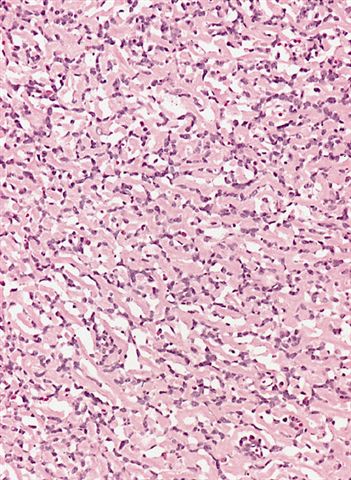

- Low grade

- Paucicellular with monomorphic, stellate or fusiform shaped cells without atypia; striking in their blandness, so much so that any significant pleomorphism should cause one to pause

- Prominent plexiform vasculature (delicate thin walled arborizing and curving capillaries that form a network reminiscent of chicken wire fencing)

- These are striking because of the overall background paucicellularity and are still present in high grade tumors but are much less obvious

- Numerous signet ring lipoblasts, particularly at periphery of lobules

- This imparts a lipoblastoma-like appearance (see Differential diagnosis)

- Mucoid matrix is rich in hyaluronic acid that may form large mucoid pools (so called pulmonary edema pattern)

- Will be positive for stromal mucin stains such as Alcian blue (see Microscopic (histologic) images)

- Typically there is no significant mitotic activity